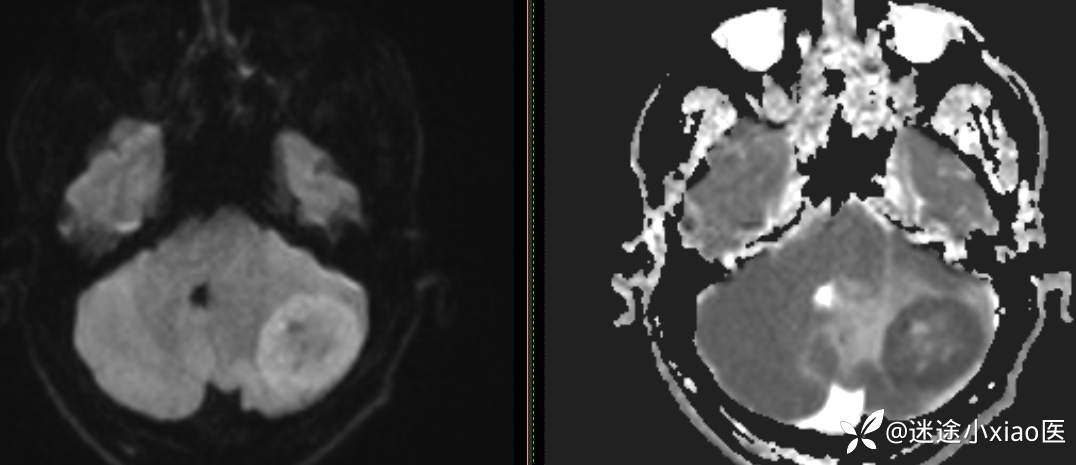

头颈组15:男,62岁,左侧小脑半球占位,原发?转移?是否有意外?

主 诉: 头晕、恶心呕吐半月余。

现病史: 患者半月前无明显诱因下明显头晕,伴恶心呕吐,无意识丧失、无智力明显下降,无视物模糊,无耳鼻腔出血,无四肢抽搐、畸形,无胸闷气促、呼吸困难。

既往:膀胱癌手术史。